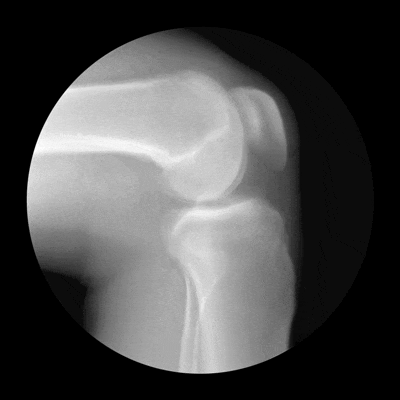

在亚洲地区,每6个人中就有1人在一生的某个阶段患上关节炎这种世界头号致残性疾病。在中国50岁以上人群中,膝骨关节炎患病率达14.3%,是中老年人致残的主要原因。

膝关节一出现毛病,很多人就不知道该怎么办了。有人认为运动好,有人认为要静养。大家各持己见,众说纷纭。其实,关于膝关节如何保护,人们存在很多误区。关节炎的患者常常伴随疼痛的症状,运动时常引起疼痛或加重疼痛,从而认为运动会进一步损害关节。

然而,在医学上,运动已被证实对关节炎患者是获益的。